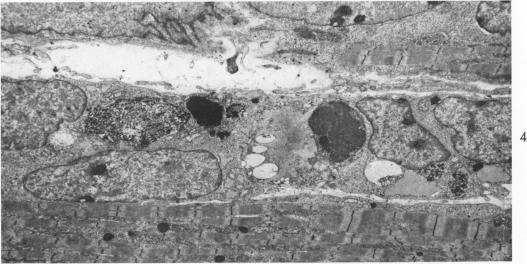

HISTOLOGIC ALTERATIONS IN PRECLINICAL MOUSE MUSCULAR DYSTROPHY.

Am J Pathol. 1964 Jun;44(6):931-46.